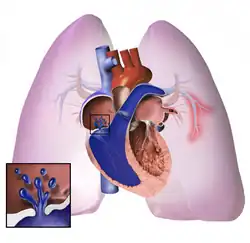

.jpg)

The pathogenesis of pulmonary arterial hypertension (WHO Group I) involves the narrowing of blood vessels connected to and within the lungs. This makes it harder for the heart to pump blood through the lungs, as it is much harder to make water flow through a narrow pipe as opposed to a wide one. Over time, the affected blood vessels become stiffer and thicker, in a process known as fibrosis. The mechanisms involved in this narrowing process include vasoconstriction, thrombosis, and vascular remodeling (excessive cellular proliferation, fibrosis, and reduced apoptosis/programmed cell death in the vessel walls, caused by inflammation, disordered metabolism and dysregulation of certain growth factors).[27][28] This further increases the blood pressure within the lungs and impairs their blood flow. In common with other types of pulmonary hypertension, these changes result in an increased workload for the right side of the heart.[16][29] The right ventricle is normally part of a low pressure system, with systolic ventricular pressures that are lower than those that the left ventricle normally encounters. As such, the right ventricle cannot cope as well with higher pressures, and although right ventricular adaptations (hypertrophy and increased contractility of the heart muscle) initially help to preserve stroke volume, ultimately these compensatory mechanisms are insufficient; the right ventricular muscle cannot get enough oxygen to meet its needs and right heart failure follows.[16][28][29] As the blood flowing through the lungs decreases, the left side of the heart receives less blood. This blood may also carry less oxygen than normal. Therefore, it becomes harder and harder for the left side of the heart to supply sufficient oxygen to the rest of the body, especially during physical activity.[30][31][11] During the end-systolic volume phase of the cardiac cycle, the Gaussian curvature and the mean curvature of the right ventricular endocardial wall of PH patients were found to be significantly different as compared to controls.[32]